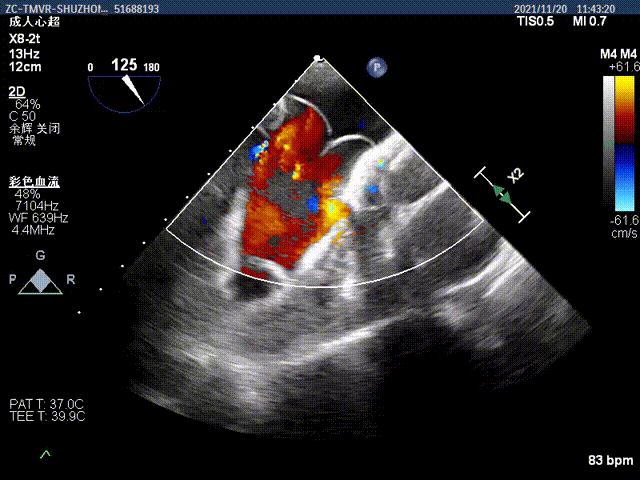

手术采用左侧第六肋间微创切口心尖入路,在超声引导下,清晰识别MitraFix®输送系统准确跨瓣,并将人工瓣膜准确释放于二尖瓣瓣环,术中超声发现局部介入瓣环位置偏低,及时换为手动输送器固定模式,精细调整介入瓣的左心房伞盘位置,最终瓣膜释放后支架贴合牢固,无瓣周漏及瓣内返流,二尖瓣前向血流通畅,左心室流出道通畅,流出道血流速度为2.4 m/s. 顺利撤出输送系统,关闭心尖切口无出血,手术顺利结束。患者射血分数仅30%左右,心脏功能差,麻醉后血压一度需要多巴胺和肾上腺素等药物维持,瓣膜置换后即刻血压升高,出手术室时候所有血管活性药物全部减停了。第二天顺利拔除气管插管。

术前二尖瓣重度反流

人工二尖瓣启闭良好